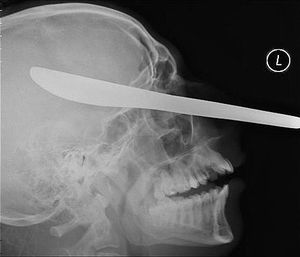

The X-ray of a miracle stab victim who had a BUTTER KNIFE embedded in his skull through the side of his nose

This blunt blade lodged ended up just an inch from the brain, and was removed in an emergency surgery in order to avoid bleeding or meningitis, an expected complication.